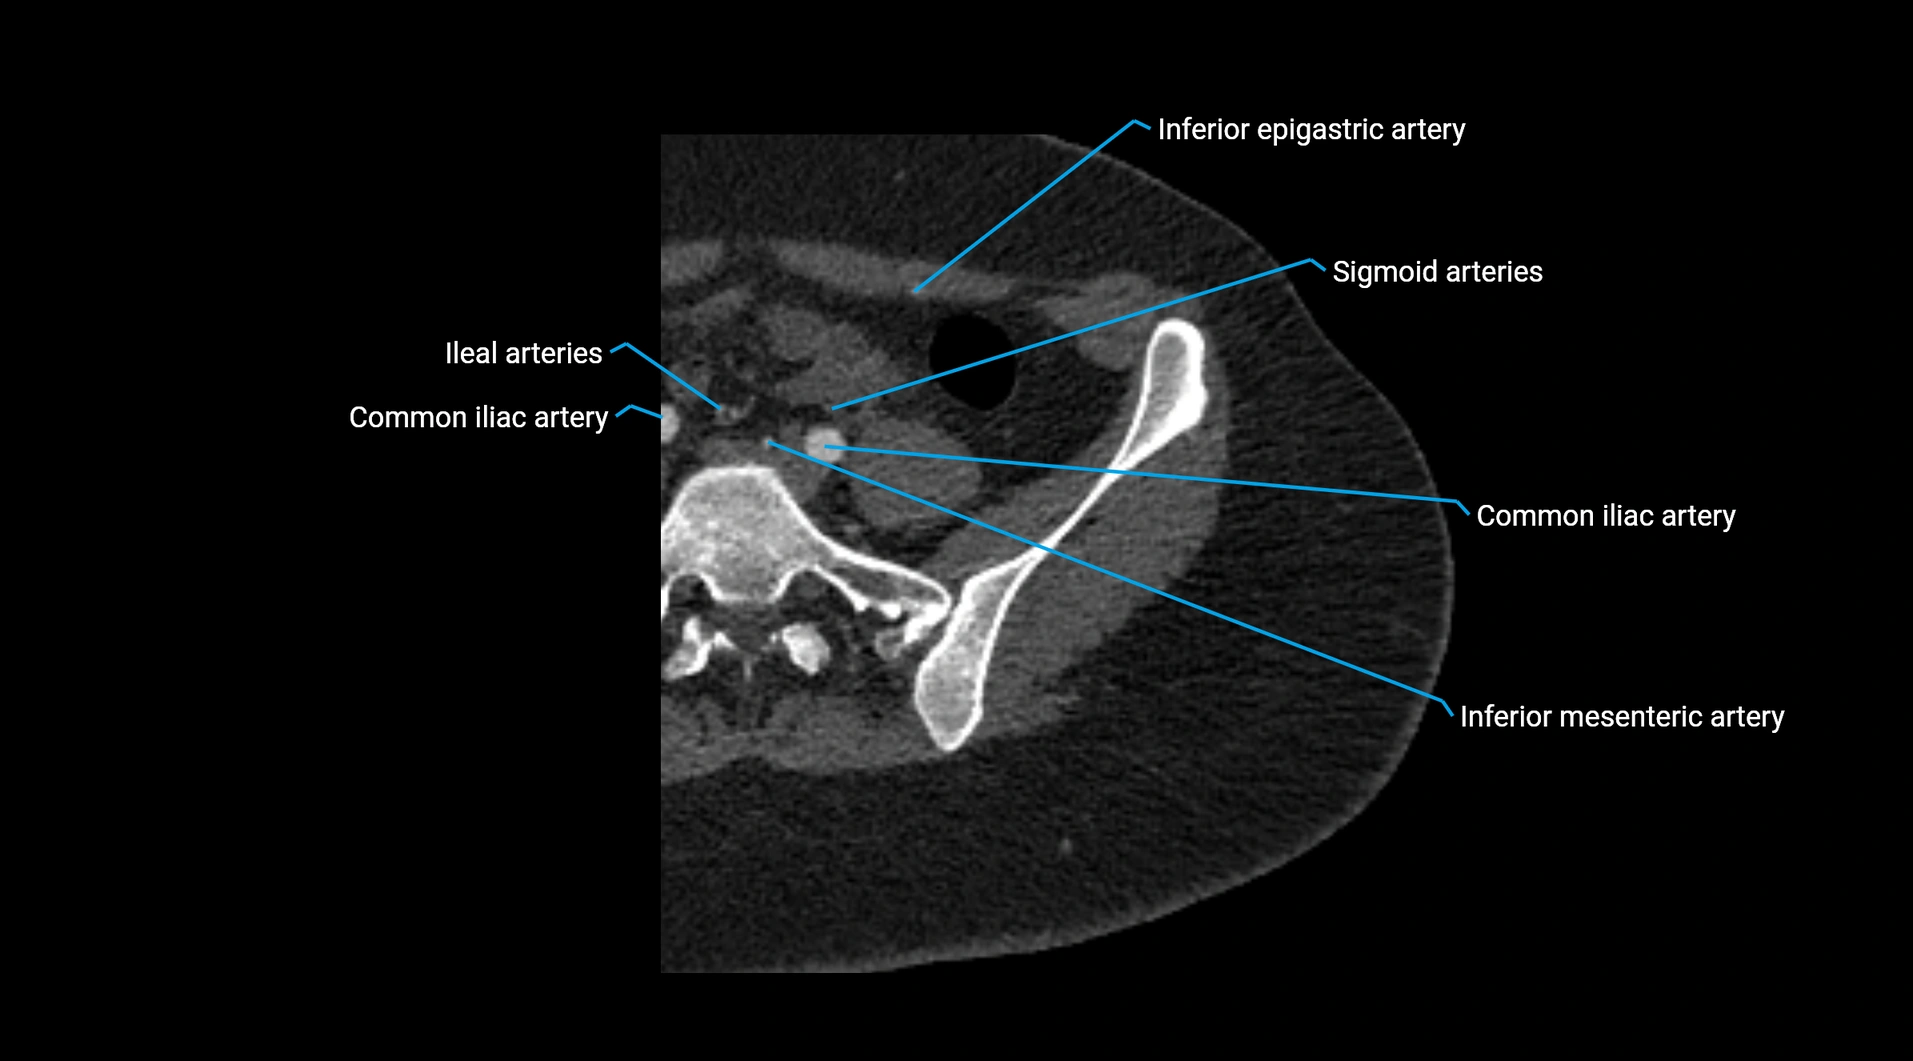

CT images

image